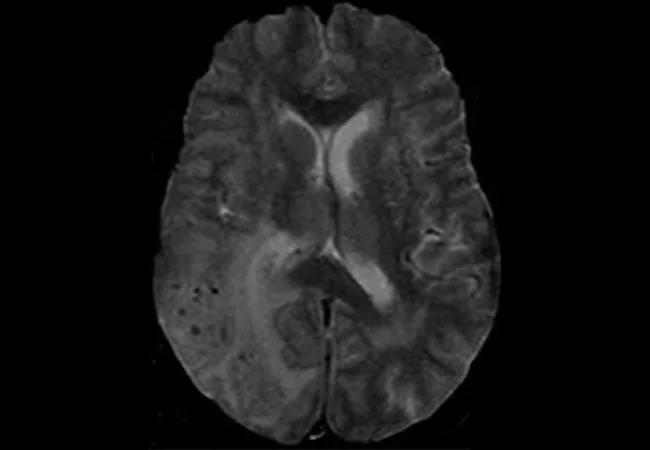

brain MRI showing inflammation related to cerebral amyloid angiopathy

Image at top: Brain MRI of a patient at the time of CAA-RI diagnosis. Reprinted from Amin et al., “The prevalence of radiological cerebral amyloid angiopathy-related inflammation in patients with cerebral amyloid angiopathy,” Journal of Stroke and Cerebrovascular Diseases (2023 Oct 26;32[12]:107436), © 2023, with permission from Elsevier.